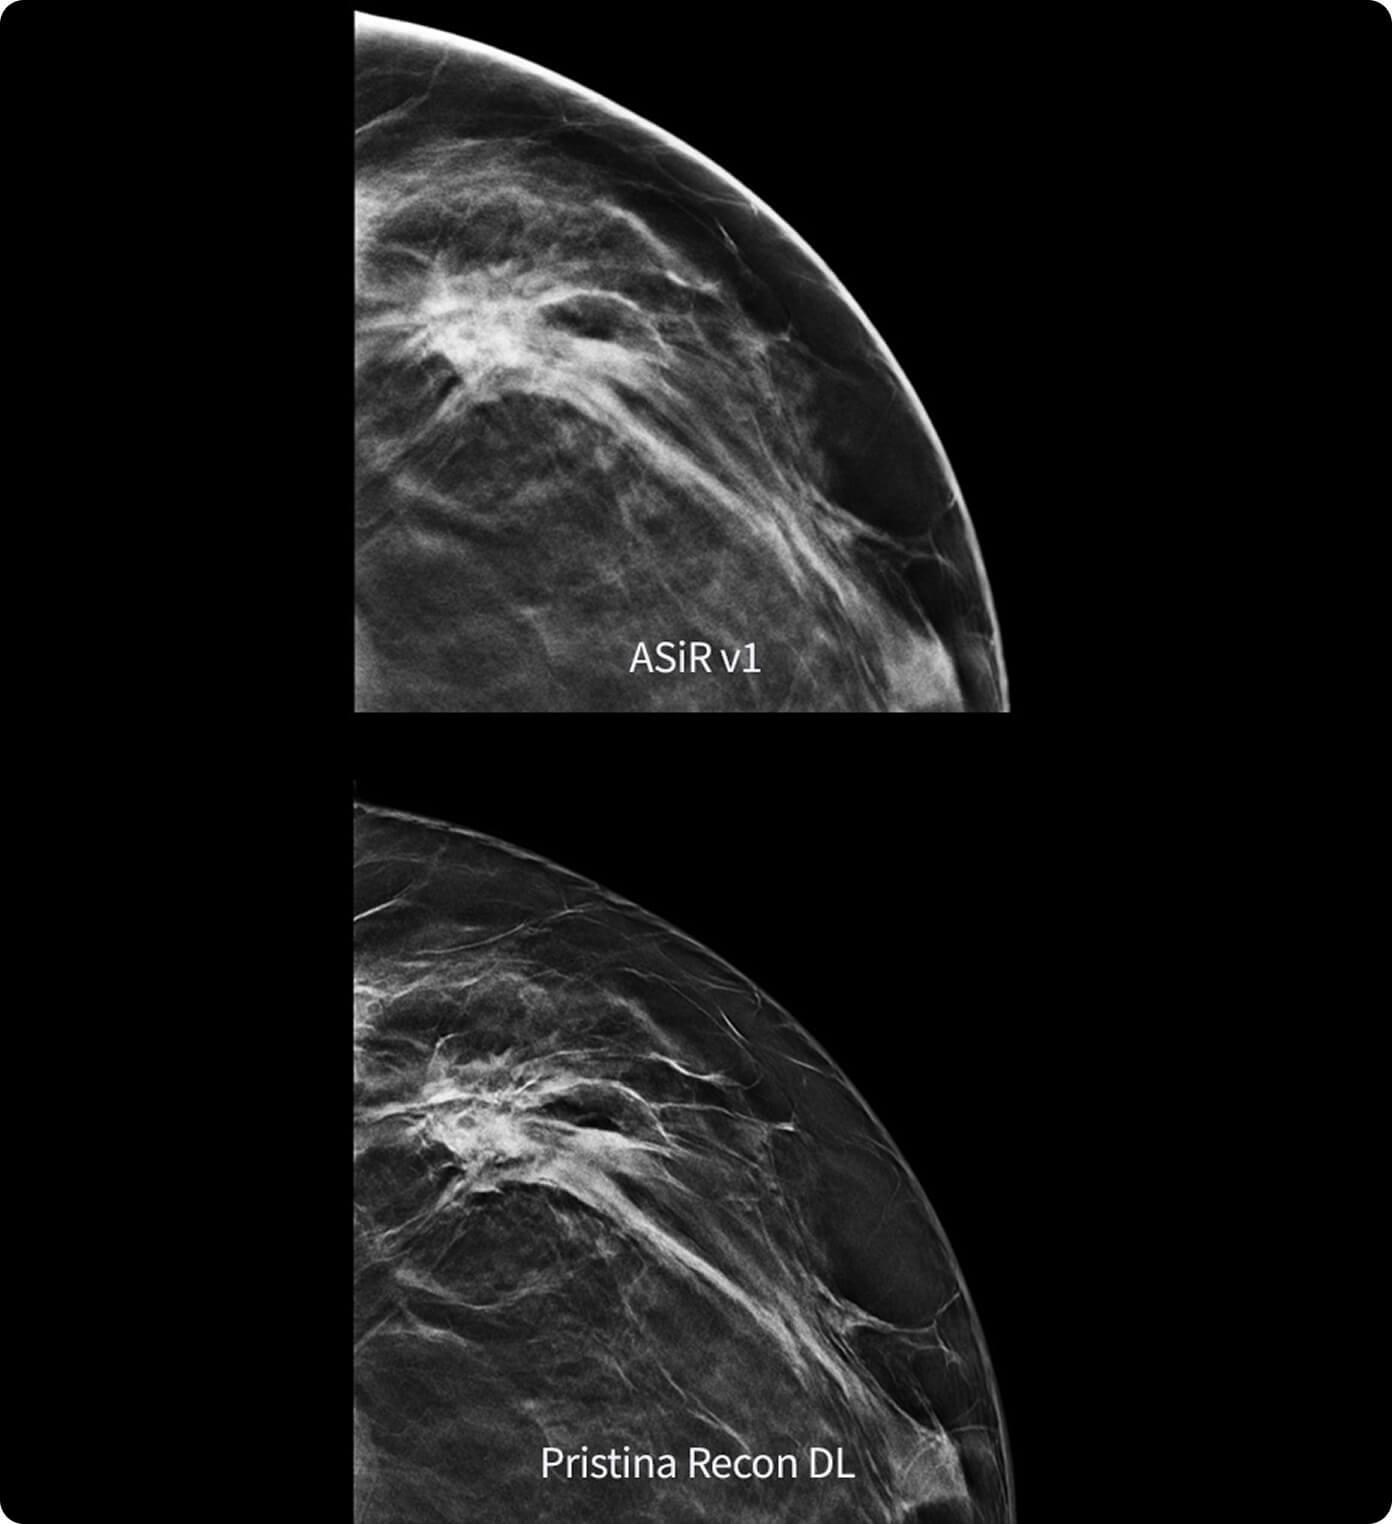

La netteté et la qualité image globale ont été privilégiées dans plus de 99 % des évaluations d’images¹

Sa technologie à double réseau de deep learning révèle des détails fins tout en réduisant les artefacts et le bruit perçu1,2, sans augmenter la dose.

Grâce à deux modèles avancés d’intelligence artificielle, la qualité d’image est améliorée sans modifier l’acquisition.

L’amélioration est évidente : les radiologues interrogés préfèrent systématiquement sa netteté1,2 et la visibilité des lésions1,2.

1. Étude de préférence réalisée sur 140 cas d’étude avec 8 radiologues agréés MQSA, formés à l’évaluation de la qualité d’image clinique par l’ACR, comparant Pristina Recon DL à ASiR v1.

2. Évaluation des performances de lecture sur 19 680 lectures avec 8 lecteurs, utilisant des données cliniques modélisées, comparant Pristina Recon DL et ASiR v1.